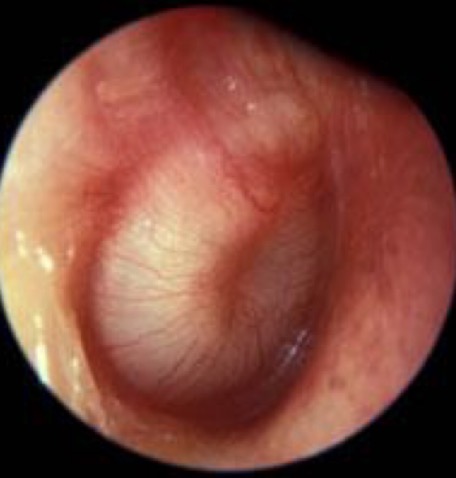

Comment on this tympanic membrane

Red and inflamed

Still translucent

However, not completely infected

May be an upper respiratory tract infection e.g. flu/cold